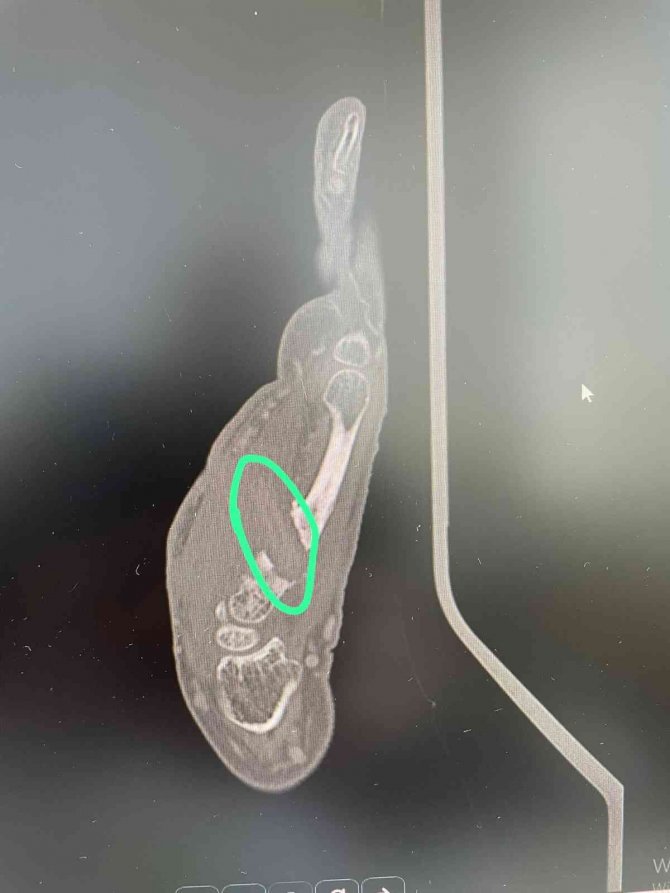

Her geçen gün elinin acısının şiddetini arttırdığını ve elinin hem ön hem de arka tarafından derisinin delinerek akıntı olmaya başladığını belirten Raziye Baş, "Kalça kırığı çok acı veren bir durum olmasına rağmen elimin acısından durmaz hale geldim. Tekrar hastaneye geldim. Günlerce hastanede yattım. Kolumdan film ve MR çekilmesine rağmen kimse bu film ve MR'a bakmadı. Enfeksiyon geçer diye tam 7 ay beklettiler. Kolumu kullanamaz ve yalnız başıma hayatımı sürdüremez hale geldim. Bir yakınımın tavsiyesi ile bu defa İzmir'e başka bir hekime gittim. Doktor beraberimde götürdüğüm film ve MR'ı bakar bakmaz içeride bir cisim olduğunu belirtip hemen ameliyata aldı. Elimin içinden büyük bir odun parçası çıkarıldı. Kısa sürede sağlığıma kavuştum" diyerek kendisini aylardır acı çektiren kişi ve kişilerden şikayetçi olduğunu söyledi.

İlk gittiği hastanede çekilen film ve MR'ı da paylaşarak yaşadığı acının sıradan bir sağlık sorunu değil tamamen ihmalden kaynaklandığını ileri süren Raziye Baş, "Ben "canım çok yanıyor elimi hareket ettiremiyorum" dedikçe Aydın'daki doktor beni tembellikle suçladı. "Tembel olduğun için elini hareket ettirmiyorsun" deyip benim psikolojimi de bozdular. İnsan önündeki film ve MR'a bakmaz mı? Bana 7 ay boyunca adeta işkence ettiler" diyerek yaşadıklarına isyan etti.